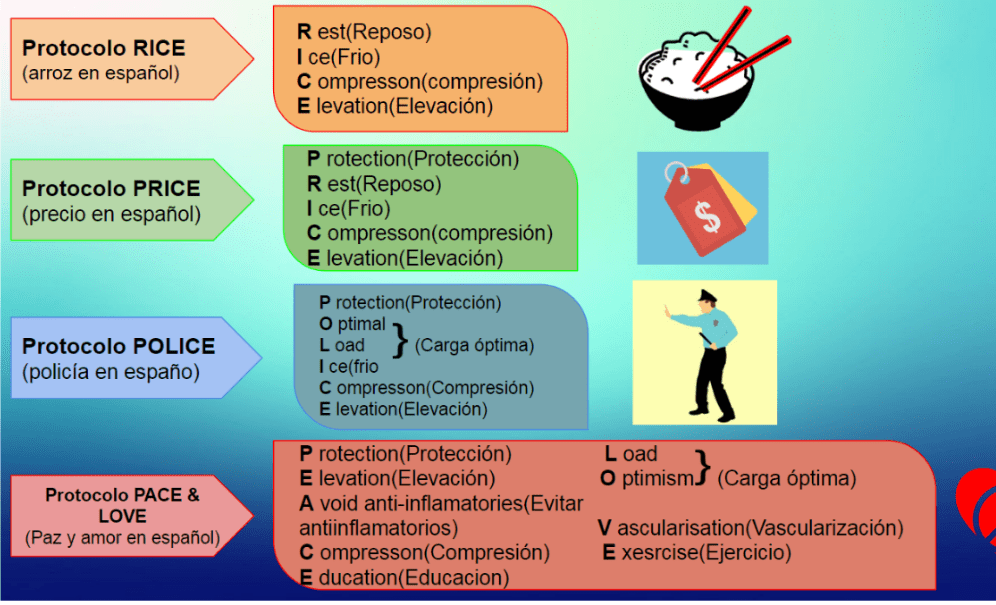

Existen protocolos iniciales que han sido cambiando y mejorando para optimizar la pronta recuperación, es importante remarcar que estos protocolos deben ser indicados por profesionales de la salud capacitados puesto que trabajamos en las primeras horas y días después de que ocurra la lesión, donde el cuerpo empieza la reparación de los tejidos.

Existen protocolos recomendados para tratar (dependiendo del personal medico y su indicación).

Protocolo RICE (Arroz en español)

- R: Rest (Reposo)

- I: Ice (Hielo)

- C: Compresson (Elevacion)

Protocolo PRICE (Precio en español)

- P: Protection (Proteccion)

- R: Rest (Reposo)

- I: Ice (Hielo)

- C: Compresson (Compresión)

- E: Elevation (Elevación)

Protocolo POLICE (Policia en español)

- P: Protection (Proteccion)

- O: Optimal (Carga optima)

- L: Load (Carga optima)

- I: Ice (Hielo)

- C: Compresson (Compresión)

- E: Elevation (Elevacion)

Protocolo PACE & LOVE (Paz y amor en español)

- P: Protection (Protección)

- E: Elevation (Elevación)

- A: Avoid anti-inflamatories ( Evitar anti-inflamatorios)

- C: Compresson (Compresión)

- E: Education (educación)

- L: Load (Carga óptima)

- O: Optimism (Carga óptima)

- V: Vascularisation (Vascularización)

- E: Exesrcise (Ejercicio)

Protocolo POLICE y PACE & LOVE

Siendo el protocolo POLICE y PACE & LOVE los más usados, puesto que los anteriores su evidencia de efectividad es comprometida, ya que indican reposo y si bien es importante disminuir la actividad en las zonas afectadas, se a encontrado que el reposo puede llevar a debilidad muscular, inestabilidad articular e incluso adherencias (limitación al movimiento producto de una incorrecta regeneracion de los tejidos)